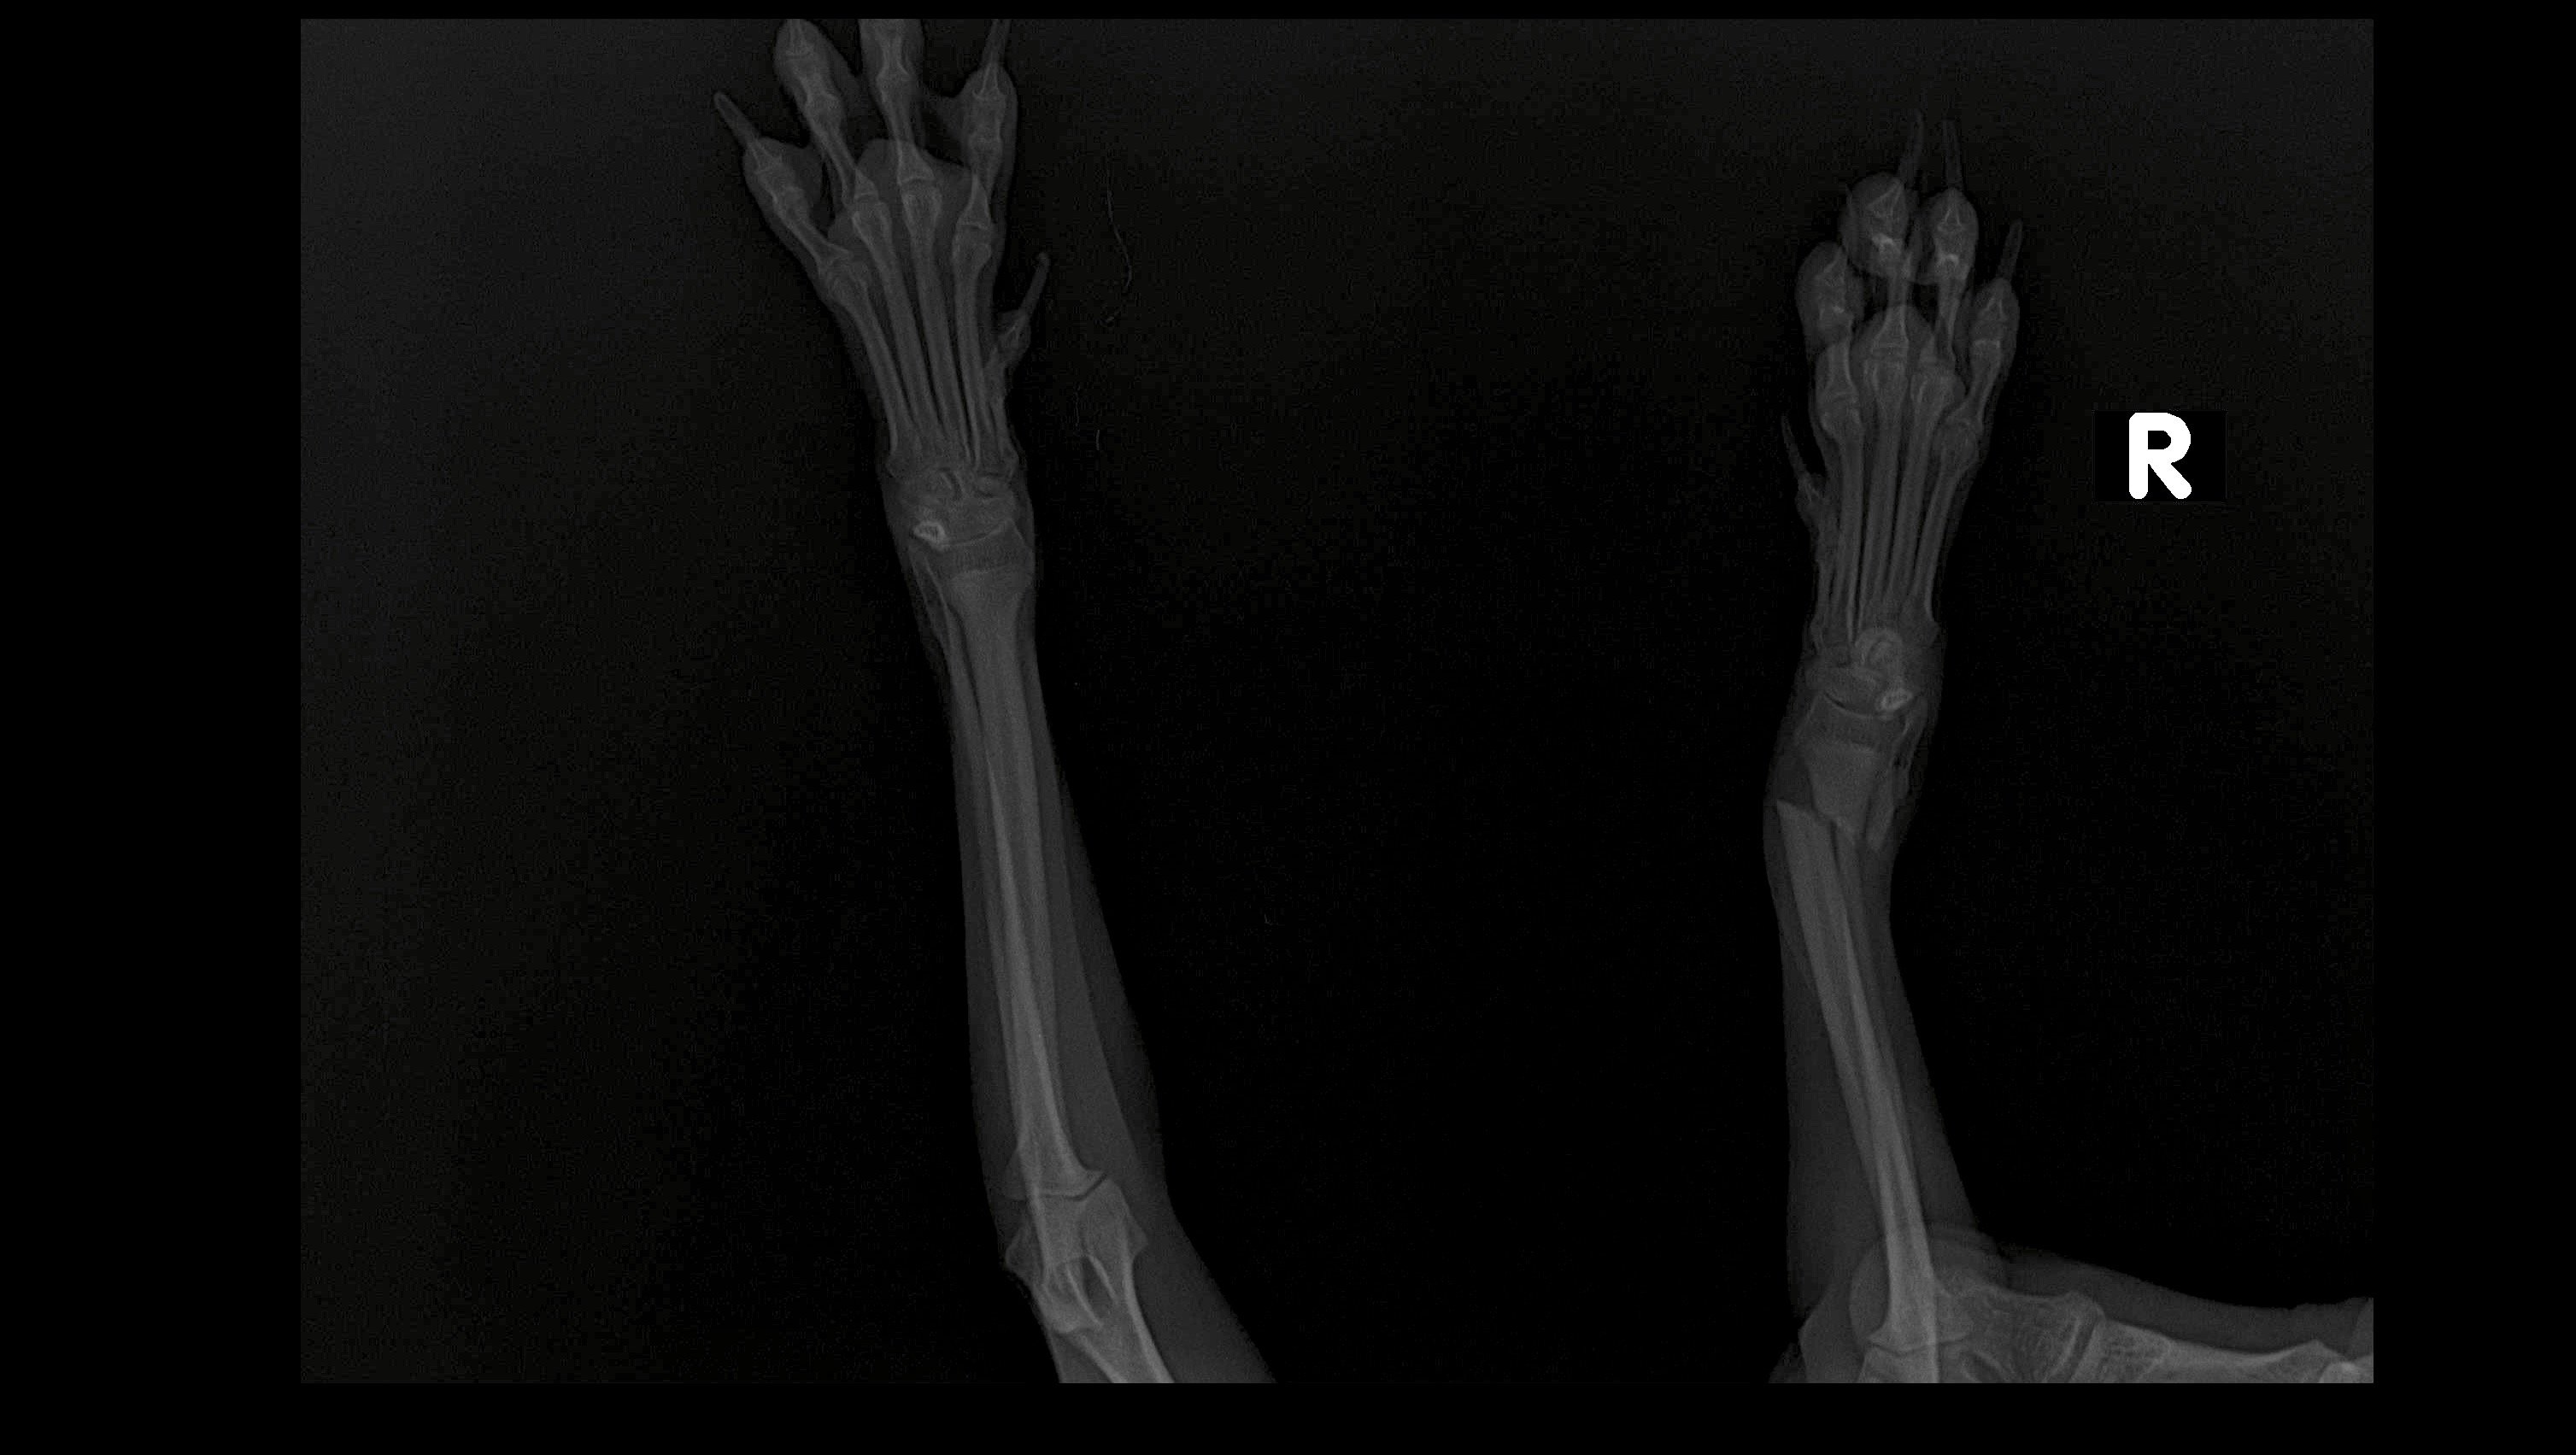

Hace unos días, mientras bajaba las escaleras con mi hermano, tropecé y caí. El golpe fue tan fuerte que me rompí dos huesos de mi patita. Ahora necesito una cirugía urgente en los próximos 6 días, pero el costo es alto y mi familia no puede cubrirlo todo.

Pero ahora estoy así: